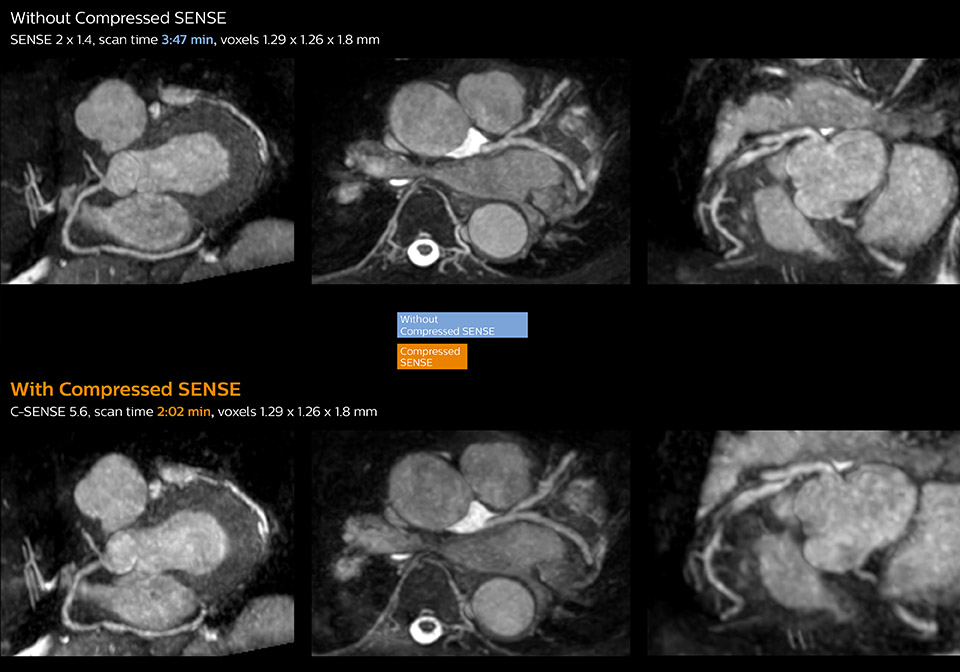

These images of a patient with acute myocardial infarction images were acquired on Ingenia 1.5T with and without Compressed SENSE.

These images with and without Compressed SENSE were acquired on Ingenia 1.5T.